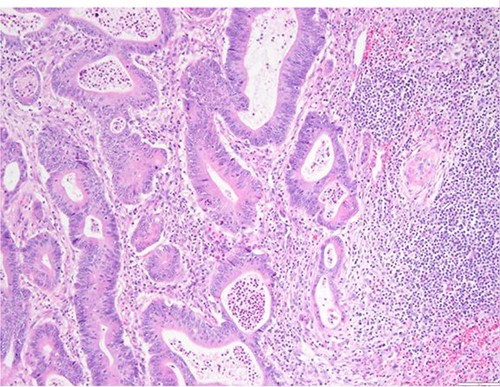

The definitive pathological report revealed adenocarcinoma metastases with morphology and immunophenotype compatible with an intestinal origin, both in splenic parenchyma and in uterine myometrium (see Figs 1–8).

Surgical specimen: hysterectomy; microscopy, HE; endometrium and myometrium infiltrated by well-formed neoplastic glandular structures composed of cells with ‘pencillated’ and atypical nuclei, with nucleoli, apoptosis and mitotic figures, consistent with an intestinal origin (metastatic colorectal adenocarcinoma).

Surgical specimen: hysterectomy; microscopy, HE; endometrium and myometrium infiltrated by metastatic colorectal adenocarcinoma.